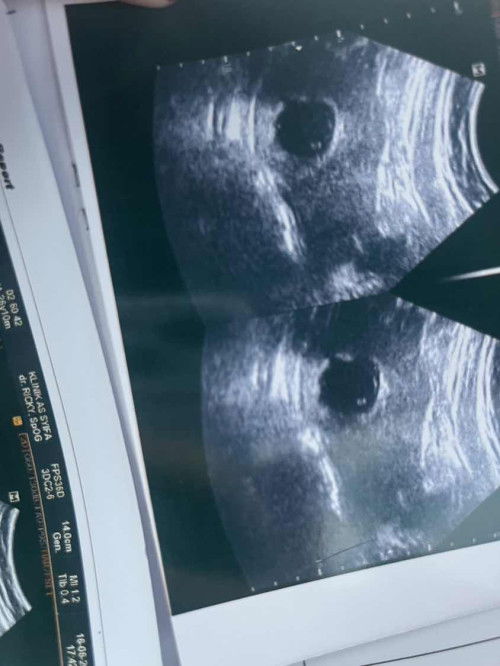

Hallo bun, jadii aku udah periksa lagi setelah 12 minggu, jadii tetap di bilang hamil kosong!

Lanjut sini yah bun, terus disuruh kuret. Tapi sampai detik ini aku gak ada flek, gak ada sakit keram perut, akhirnyaa mintak obat dulu, tapi belum berani jugaaa minum yahh.

9 week hari ini , hpht 31 maret

Bun, aku baru usg, 9 week tapi masih kantong, disuruh kurek aku bun😭🥹 ada yang ngalmin sama bun